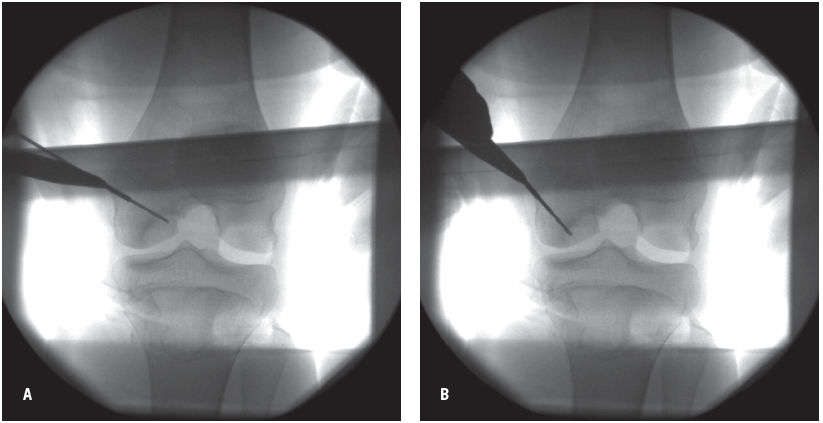

Figures 3A and 3B – Intraoperative fluoroscopic images of antegrade drilling with multiple holes into the osteochondritis dissecans lesion. Care is taken to avoid penetration of the intact articular cartilage and the open growth plate.

For stable lesions requiring surgical intervention, drilling of the osteochondritis dissecans lesion is effective at promoting an intrinsic healing response (Figures 3A and 3B). Using this technique, small channels are drilled into the subchondral bone near the site of the lesion, allowing for the influx of healing elements such as mesenchymal stem cells and growth factors.6,9 Unstable, nondisplaced osteochondral fragments (grade III lesions) often can be stabilized with screw fixation (Figures 4, 5, and 6). Unstable, displaced osteochondral fragments (grade IV lesions) that are not salvageable often require surgical techniques involving osteochondral tissue (autograft or allograft) or autologous chondrocyte implantation.2